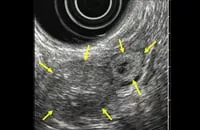

EUS画像(インスリノーマ例)

局在診断に関しては、CTや内視鏡的超音波断層検査(EUS)で腫瘍が分かる場合もありますが、腫瘍が描出されない時には、カルシウムを用いる選択的動脈内刺激薬注入試験(SASI Test)を行います。